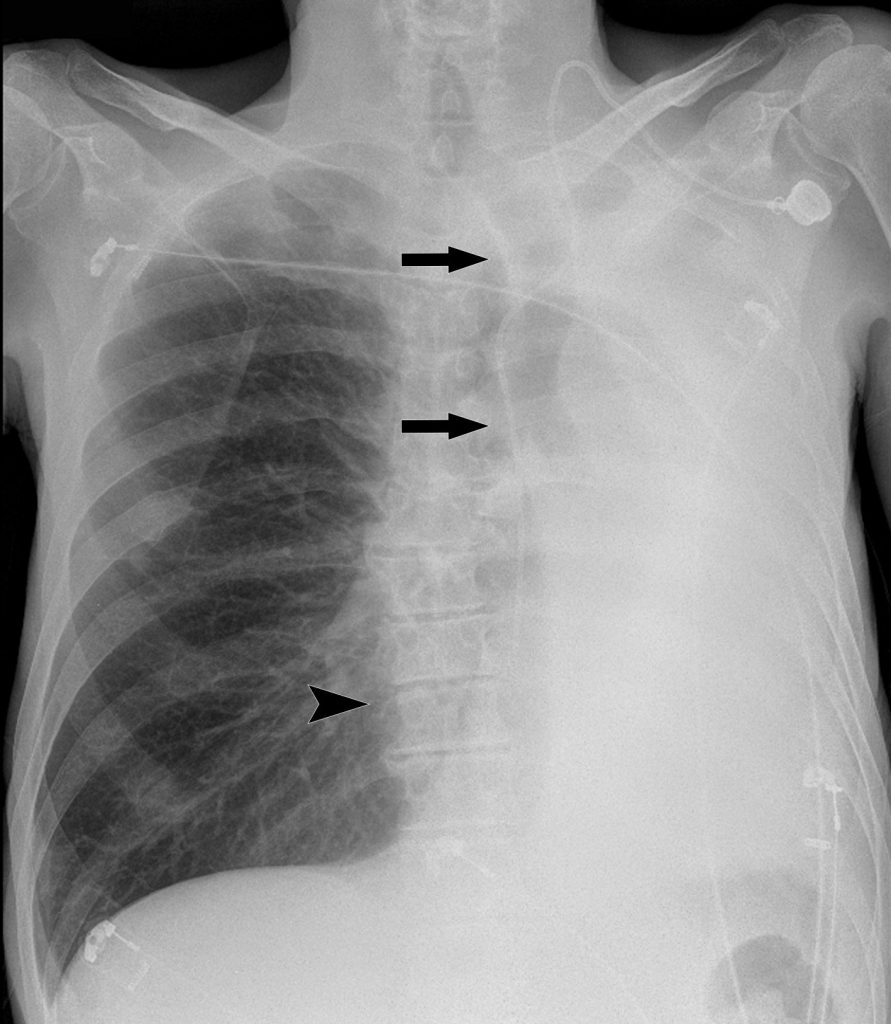

Fig. 91.7. Radiographie de face couchée d’une atélectasie pulmonaire gauche.

L’hémithorax gauche est entièrement opaque. La trachée (flèches) et le médiastin sont attirés du côté de l’hémithorax radio-opaque, témoignant de la perte de volume. Le déplacement du médiastin vers la gauche démasque le bord droit du rachis (tête de flèche).

Source : CERF, CNEBMN, 2022.